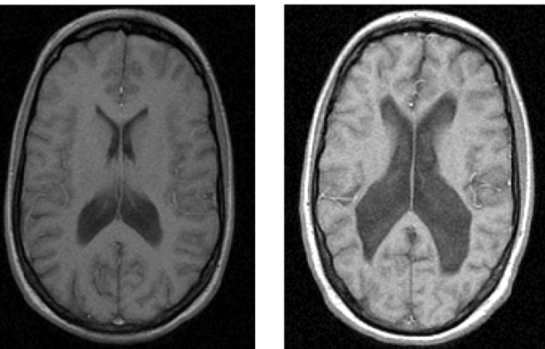

Describe the structural changes of brain in schizophrenia patients [3]

Larger ventricles and

smaller mesial temporal lobe structures:

• Ventricular enlargement is around 25%

• Overall reduction in brain volume of around 2%

• Greater reduction in grey matter compared to normal populations